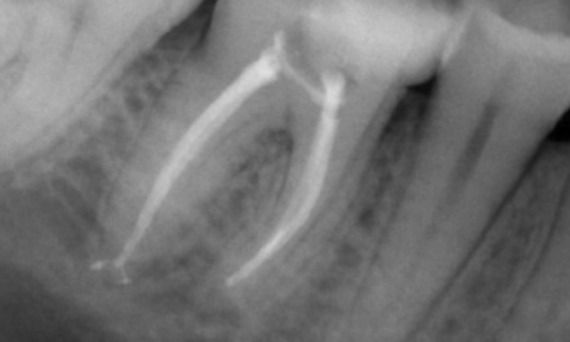

"Escolhi a TruNatomy para poder preservar o máximo de dentina possível para superar a carga oclusal e aumentar a longevidade do dente." - Dr. Abuelezz

Antes: No exame, havia uma lesão de cárie dental relacionada ao primeiro molar inferior direito. O exame radiográfico revelou proximidade da lesão ao corno pulpar e, combinando-a com a queixa principal, concluiu-se um diagnóstico final de pulpite crónica irreversível.

Depois: A cavidade de acesso foi realizada da maneira mais conservadora possível. TruNatomy foi o sistema de escolha devido à idade do paciente jovem. Precisávamos preservar a dentina o máximo possível para aumentar a capacidade do dente de superar a carga oclusal e aumentar a longevidade da restauração final.

Dr. Ahmed Hussein Abuelezz (PhD em Endodontia)

Cairo, Egito